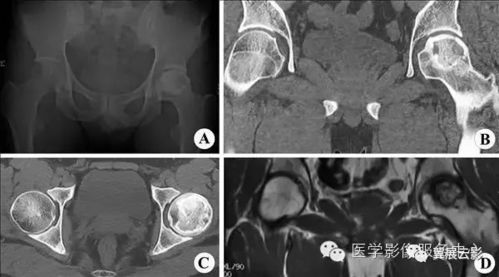

2. 多平面重建:CT数据可以通过计算机处理,生成冠状面、矢状面和任意角度的图像,为医生提供多角度观察病变的机会。

3. 三维成像:CT可以生成三维图像,有助于更直观地理解病变的位置、大小和形态。

CT扫描可以通过计算机软件对图像进行处理,实现多平面重建。这意味着医生可以从不同的角度观察病变,从而更全面地了解病情。与X光相比,CT的多平面重建技术为诊断提供了更多可能性。

CT扫描适用于各种疾病的诊断,如神经系统、心血管系统、呼吸系统、消化系统、泌尿系统等。在X光检查中,由于图像质量有限,一些疾病的诊断可能存在困难。而CT扫描可以提供更全面、准确的诊断信息。